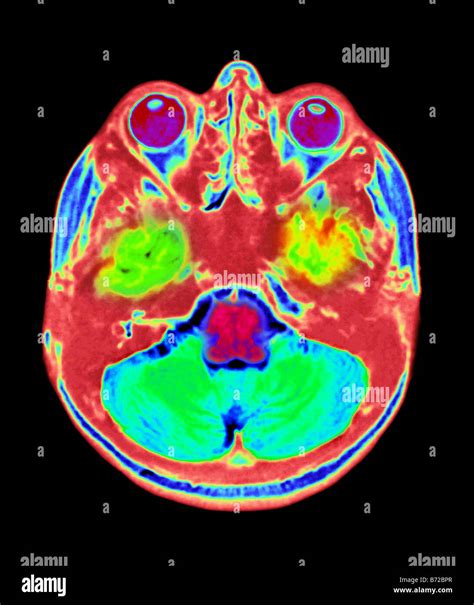

Understanding the intricacies of a Brain MRI Cage involves delving into the world of medical imaging, particularly magnetic resonance imaging (MRI). MRI is a powerful diagnostic tool that uses magnetic fields and radio waves to produce detailed images of the body's internal structures. When it comes to the brain, MRI scans are invaluable for diagnosing a wide range of conditions, from tumors and strokes to neurological disorders.

The field of MRI technology is continually evolving, with advancements that improve the quality and speed of brain scans. Some of the latest developments include:

• High-Field MRI: These machines use stronger magnetic fields, providing higher resolution images.

• Functional MRI (fMRI): This technique measures brain activity by detecting changes in blood flow, helping to map brain function.

• Diffusion Tensor Imaging (DTI): This method tracks the movement of water molecules in the brain, providing insights into the brain's white matter tracts.

• Magnetic Resonance Spectroscopy (MRS): This technique measures the levels of different metabolites in the brain, aiding in the diagnosis of certain conditions.

These advancements, combined with the use of a Brain MRI Cage, ensure that brain scans are not only accurate but also comfortable and efficient for patients.